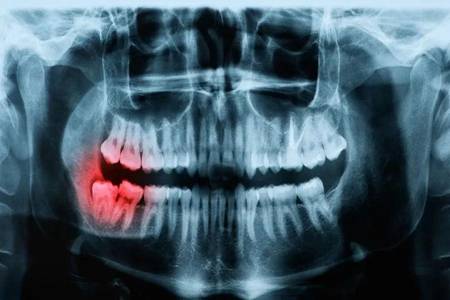

智齿一定要拔吗?智齿出现发炎肿痛时再不拔就晚了

如果你觉得智齿对于口腔问题没有影响,那么就可以不用去拔掉啊。但若是,智齿发炎肿痛的话,还不去拔?等着过年?

一时的疼痛要比一生时不时滋滋的疼好受吧?而且拔牙也没那么疼,第一步就给你上了麻醉,再加上现在的麻药工具也是在不断地更新,所以说只需要配合医生的操作,真的不是很疼。

看到这里,你可能要跃跃欲试的去拔牙了?别着急,虽然说牙齿能够顺利的拔除,但是之后也需要我们做好措施才行,不然的话很有可能出现“干槽症”哦!

这绝对不是吓唬你,因此,建议小伙伴们想要去拔掉智齿的话,在拔牙之前之后一定要选好医院以及专业的医生,之后配合医生,拔牙之后一定要谨遵医嘱,做好清洁工作,以免出现干槽症之后还要找医生进行二次清创。